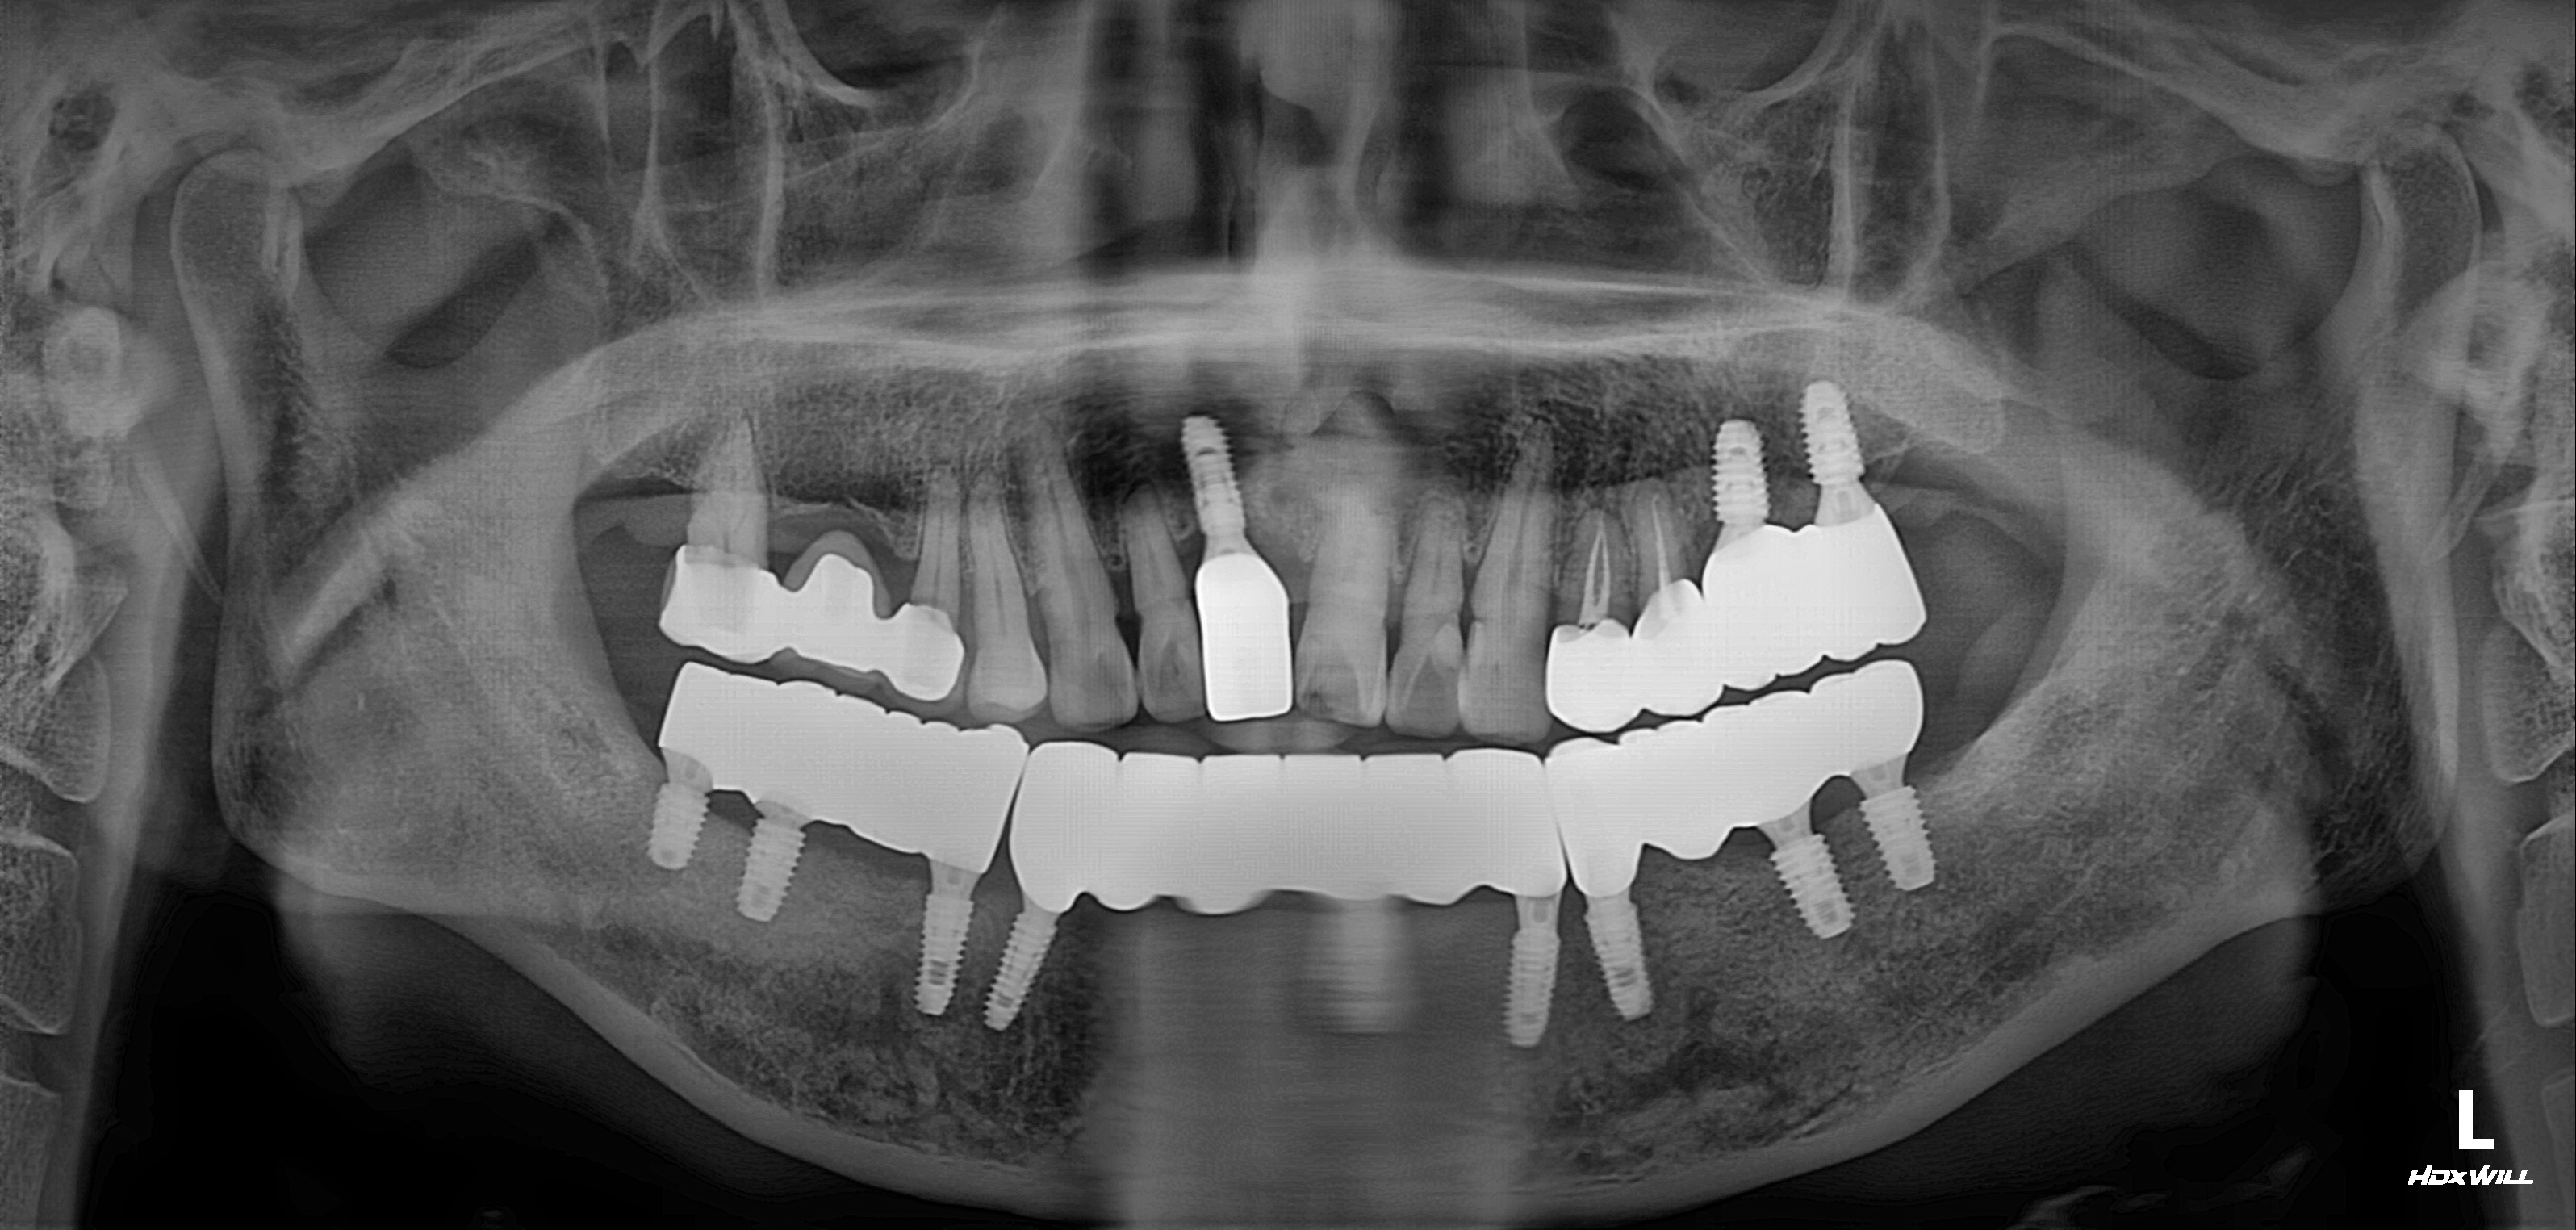

하악 전체+상악 부분 임플란트 식립사례